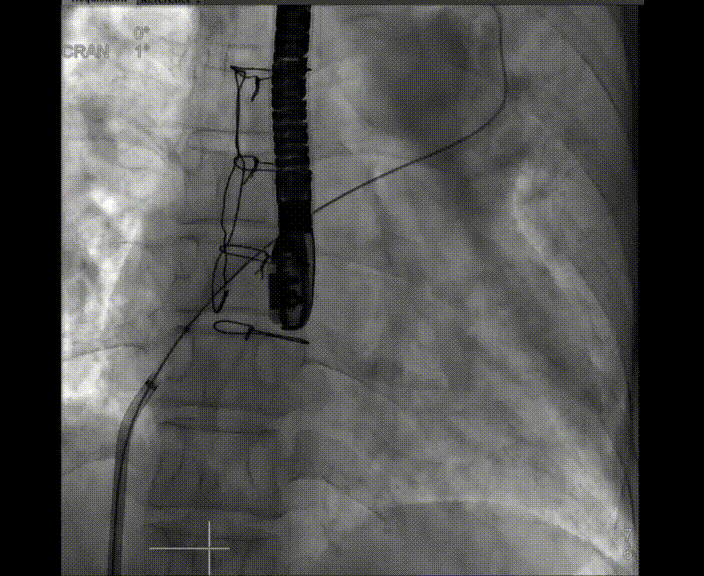

术中首先在局麻下穿刺股动脉、股静脉,完成心导管检查评估后转为全麻,在食道超声引导下穿刺房间隔,穿刺成功后将加硬导丝送入左上肺静脉建立轨道,根据患者病情行球囊预扩张后植入6mm孔径房间隔造孔支架,经透视及食道超声评估支架左右盘展开良好,夹持于房间隔两侧,固定稳定、位置良好,食道彩超显示房水平右向左为主分流,分流孔直径符合预期大小,心导管检查评估达到预期效果,释放造孔支架。术后12h患者下床活动,恢复顺利,拟于近日完善术后评估后出院。

图2.左盘在左房展开